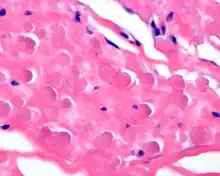

A high power photomicrograph of an elastofibroma.

By microscopie view, there is an admixture of heavy dense bands of collagenous tissue dissected by fat and abnormal elastic fibers. The elastic fibers are often quite large and are easily identified. The elastic fibers are coarse, thick, and darkly eosinophilic, often fragmented into globules, creating a "string of pearls" or "pipe cleaner" appearance. Because of degeneration, the elastic fibers will appear as globules with a serrated or "prickled" edge.[5]